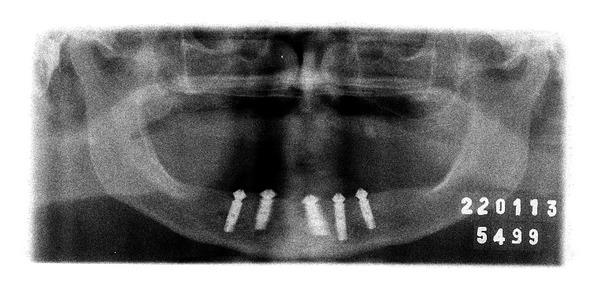

In mandibular edentulous patients, treatment based on immediate loading with rigid splinting in the mandible is well accepted; however, it is cost and time dependent, which sometimes limits this type of rehabilitation. To overcome these problems, the technique of immediate loading using a semirigid splinting extension system has been developed. Its advantages include low cost, technical feasibility, and reduced clinic time. This clinical report presents the applicability and the predictability of semirigid splinting of implants in the mandibular arch of an edentulous patient using a distal extension bar prosthesis system.

在下颌无牙患者中,基于下颌即刻负重并采用刚性夹板固定的治疗方法已被广泛接受;然而,这种方法成本较高且耗时,有时会限制此类修复方式的应用。为克服这些问题,已开发出使用半刚性夹板延伸系统进行即刻负重的技术。其优点包括成本低、技术可行性高以及临床时间缩短。本临床报告介绍了在一名无牙患者的下颌弓中使用远端延伸杆假体系统对种植体进行半刚性夹板固定的适用性和可预测性。